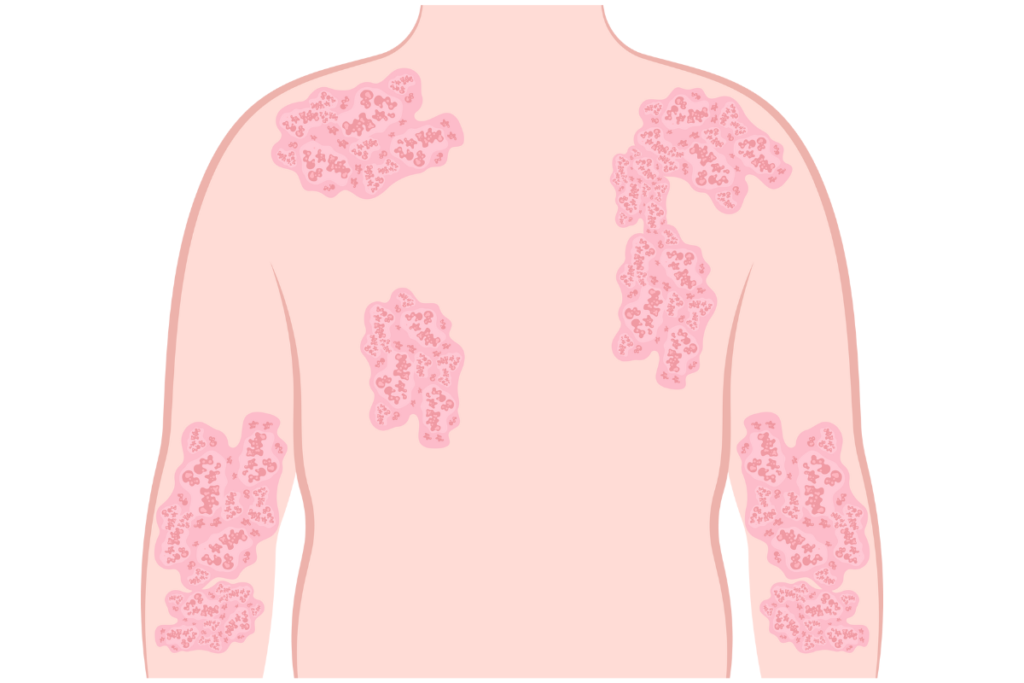

Skin Diseases

Skin is one of the main excretory organs of the body, a fact that’s easily overlooked in general. Most skin diseases are the outcome of poorly functioning detoxification systems within the body. With proper dietary reforms, exercise, and Nature Cure modalities the reduction and recovery from problems can be achieved, leading to normalcy of the skin quality.